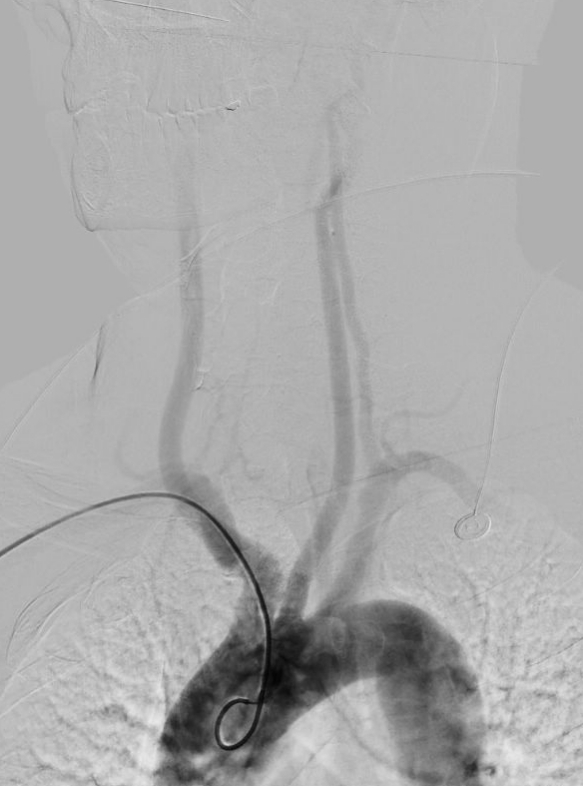

脑血管造影是目前脑血管检查的金标准,是通过动脉插管,使用造影剂显影完成脑血管检查的一种微创方法。其特点:简单、方便、安全、准确、创伤小。我院从2009年开始开展脑血管造影检查,目前开展经桡动脉、股动脉两种路径完成脑血管造影及治疗,桡动脉路径大大减轻患者的痛苦。目前开展的治疗手术:颅内外血管球囊扩张成形术、支架置入术、动脉瘤栓塞术、急症溶栓、取栓术,对于出血性脑血管病患者开展了微创血肿清除术。每年造影检查量约500例左右,治疗量约100例左右。介入技术水平走在了全市前列,取得了广大患者的好评。

图片1.jpg  图片2.jpg

经股动脉入路造影                                                               经桡动脉入路造影